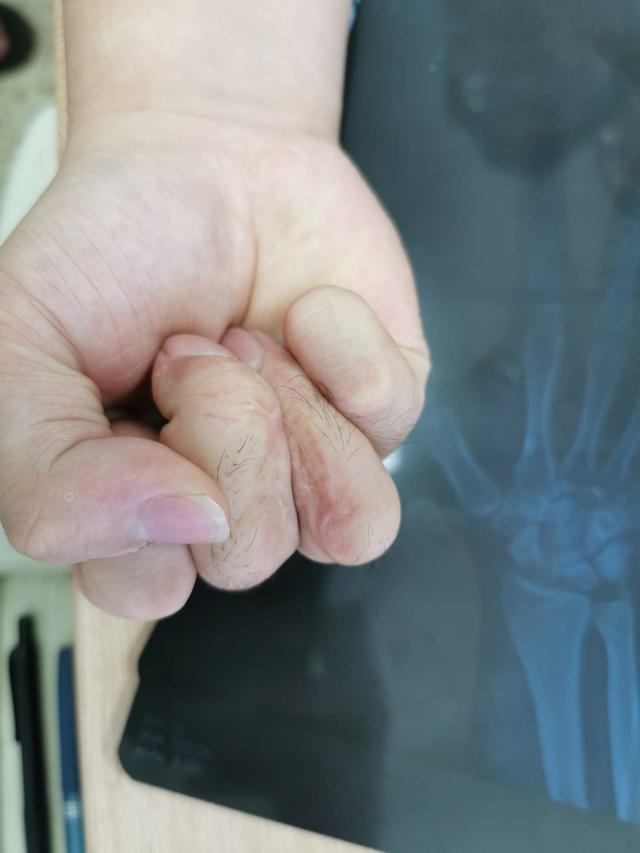

门诊收治的病人

4岁时行并指分指手术

目前患者19岁

诉求:

1、掌侧瘢痕挛缩,2、DIP侧偏畸形,3、PIP伸直受限

解决第一个问题:瘢痕条索切除,Z字成形术

第二个问题:中环指中节指骨颈V形截骨,因为孩子的伸肌腱张力较高,选择闭合截骨(短缩)

第三个问题:PIP伸直受限,考虑为中央腱松弛所致,术中紧缩中央腱,松解中指PIP掌板

并指畸形术后翻修的手术做了3个多小时

没有合适的摆锯片,用原始的方法,克氏针打孔,骨刀截骨